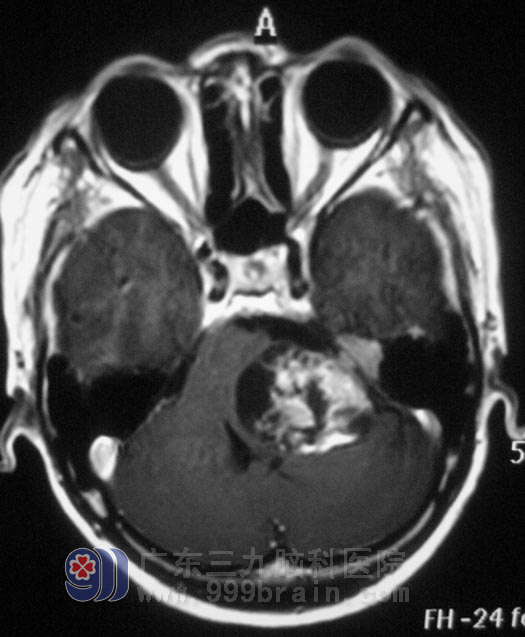

广东三九脑科医院头颅MR检查显示:左侧桥小脑角区示一不规则形囊实性占位性病变,增强后实性部分呈不均匀明显强化,囊性部分未见强化,侧面听神经增粗强化,范围约为3.6cm×4.2cm×3.7cm,周围示轻微水肿,桥脑、延髓,左侧桥臂及左侧小脑半球受压变形、移位,四脑室受压变窄,左侧内听道明显扩大。检查左耳失聪,左侧额纹、鼻唇沟较右侧轻微变浅,伸舌左偏。